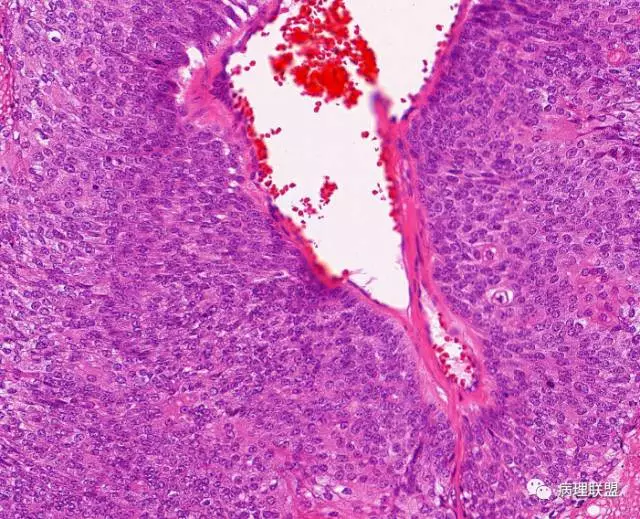

第一例和第二例病例我把典型图像压下来,是让我们以后注意,典型里找不典型,毛母质瘤主要由两种细胞构成,嗜碱细胞和影细胞构成,主要认识嗜碱细胞。

左老师,开始发的图片没有看到影细胞。最后加的图才看到了